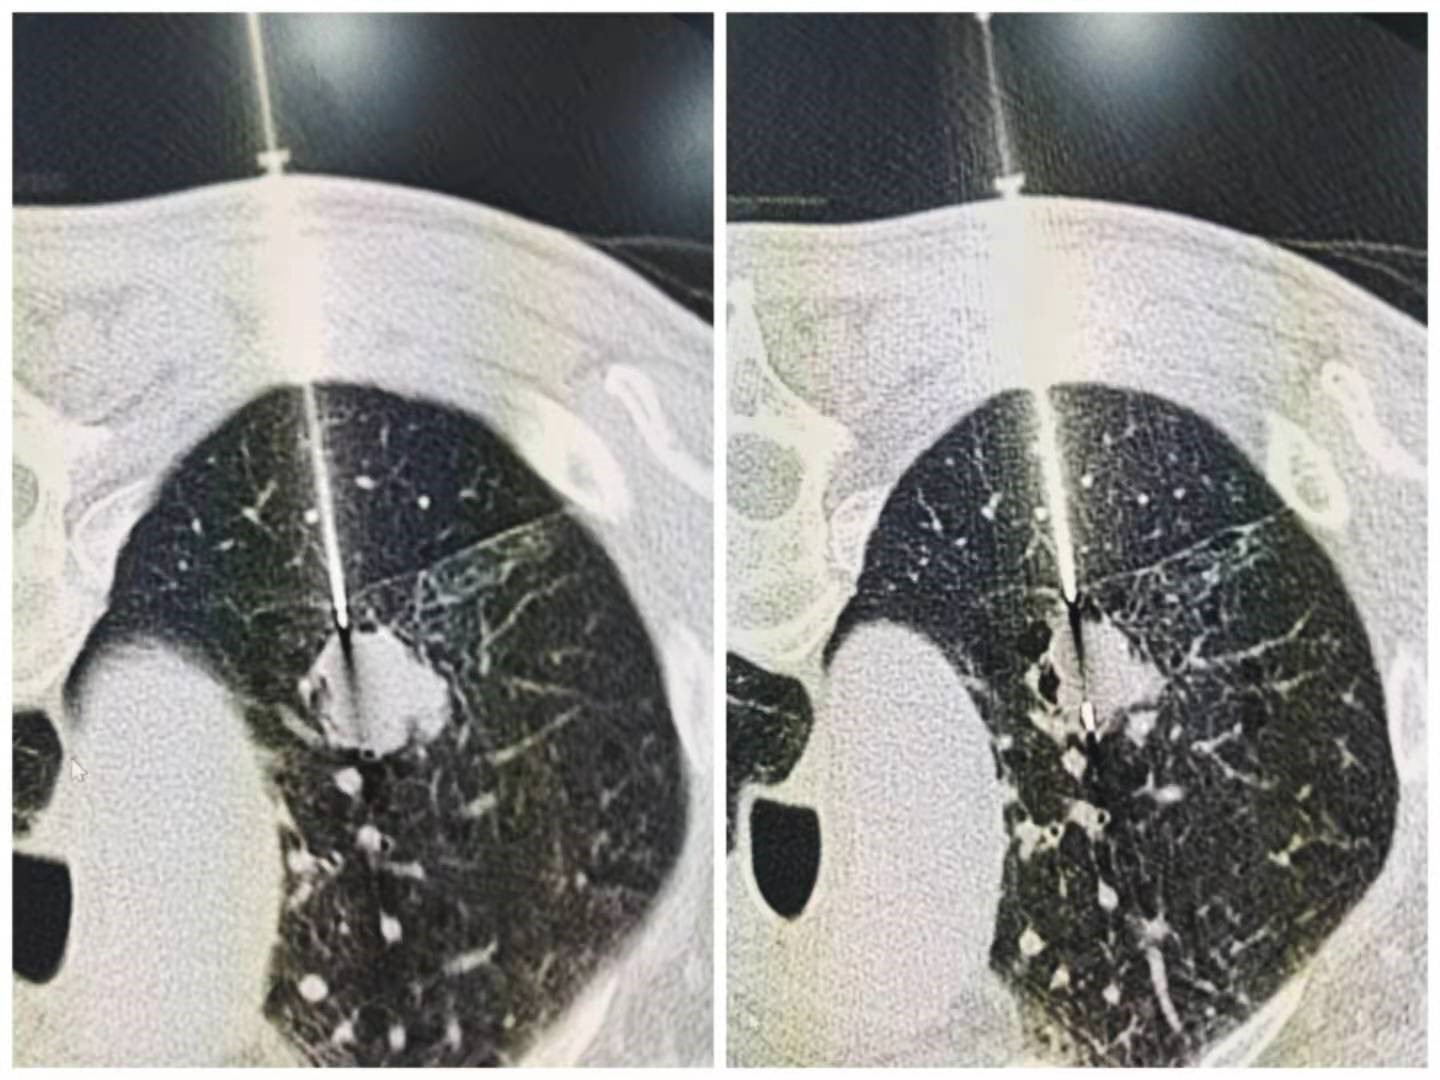

近日,我院西院影像科在介入科魏东升主任团队的鼎力支持、配合下,完成一例CT引导下经皮肺穿刺活检术。

患者郑某,61岁,男性,因两侧季肋部疼痛一年多,并伴有背部疼痛,故来我院就诊。经过相关检查,肺部CT显示:患者左肺上叶结节,纵膈及左肺门多发淋巴结肿大,胸8椎体转移、破坏,检查建议活检。为进一步系统诊治,该患者被收治肿瘤内科住院治疗。

12月11日下午,西院影像科赵海岩、介入科魏东升主任团队共同合作,历时35分钟,成功完成该患者穿刺活检术。首先,测量患者基本体征后进入已消毒CT室,训练吸气、屏气幅度,为后续穿刺准确度做准备;其次,进行胸部CT平扫+增强扫描,根据图像制定穿刺计划,并记录数值;再根据CT定位线及体表定位标识确定入针点,消毒、局麻,根据计划深度,达胸膜外进行胸膜外麻醉,进行CT扫描确认针尖与靶区关系;最后,确认进针方向无误后,引导针进入计划深度,达靶边缘。重复扫描确认针尖位置,退出引导针芯,推出活检针针芯,重复扫描确定针芯位置,击发活检针,取出标本一条。重复上述操作,取出三条标本,送检病理科。